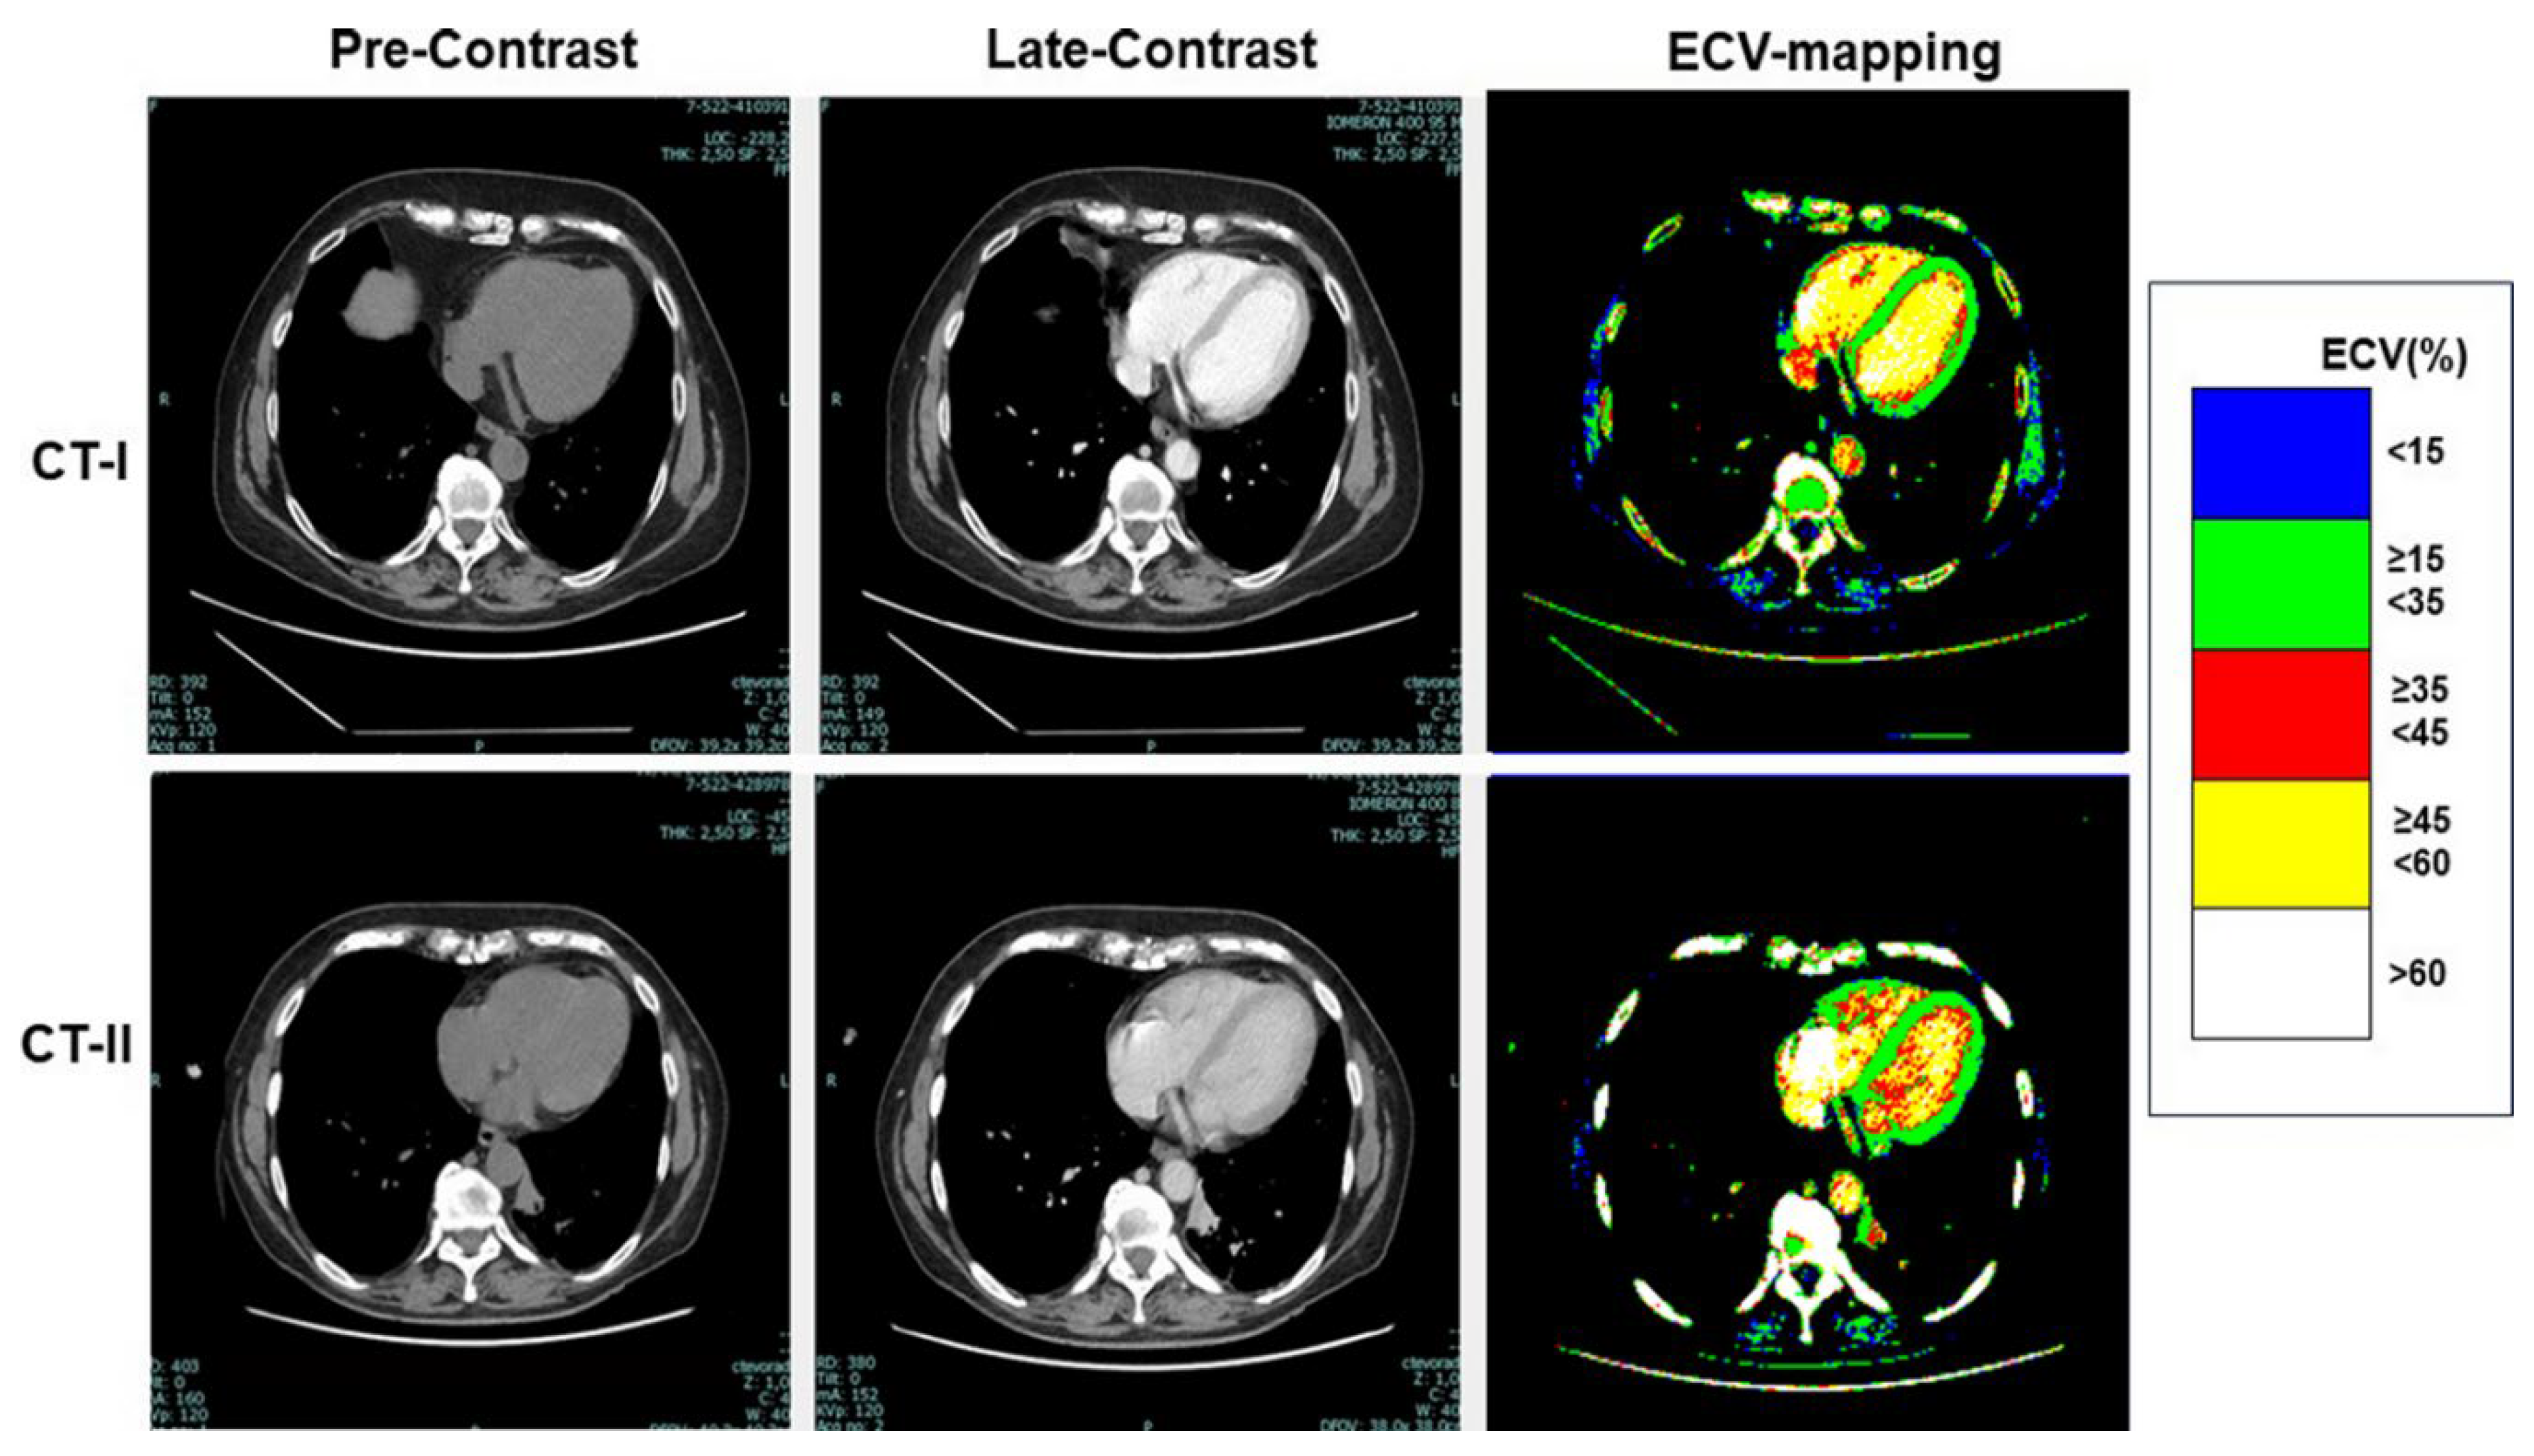

As shown in Table 3, at CT-I myocardial ECV measured in the interventricular septum and in the LV lateral wall was not significantly between High-risk and Low-risk groups, despite age and gender differences between them. Similarly, ECV of both the septum and LV lateral wall was not significantly different between the groups at CT-II. Examples of ECV maps are shown in Figure 1, Figure 2 and Figure 3.

High-risk patients showed a significant increase of both septal ECV [going from 32% (31-35%) at CT-I to 37% (35-39%) at CT-II (p = 0.0002)] and of lateral wall ECV [from 30% (27-31) to 32% (29-34) (p = 0.028)]. In contrast, the ECV change was not significant in the Low-risk group [septal ECV: from 35% (32-38) to 35% (32-39) (p = 0.16); lateral wall ECV: from 32% (29-35) to 32% (30-34) (p = 0.93)] (Figure 4). Overall, ECV increased by at least 1 percentile in 35 out of 51 (69%) High-risk patients. Among them, 15 (43%) had a diffuse myocardial increase of ECV and 20 (67%) a focal increase of ECV within the interventricular septum and/or the lateral wall.

Figure 1. Image analysis in a breast cancer patient treated with doxorubicin. Images of CT-I are shown in upper panels, whereas images of CT-II are shown in lower panels. Left-hand panels include the pre-contrast image, middle panels the late postcontrast image, and the right-hand panels the relative ECV map, respectively. As evident by the comparison of maps, a diffuse increase of ECV was found by the analysis of CT-II.